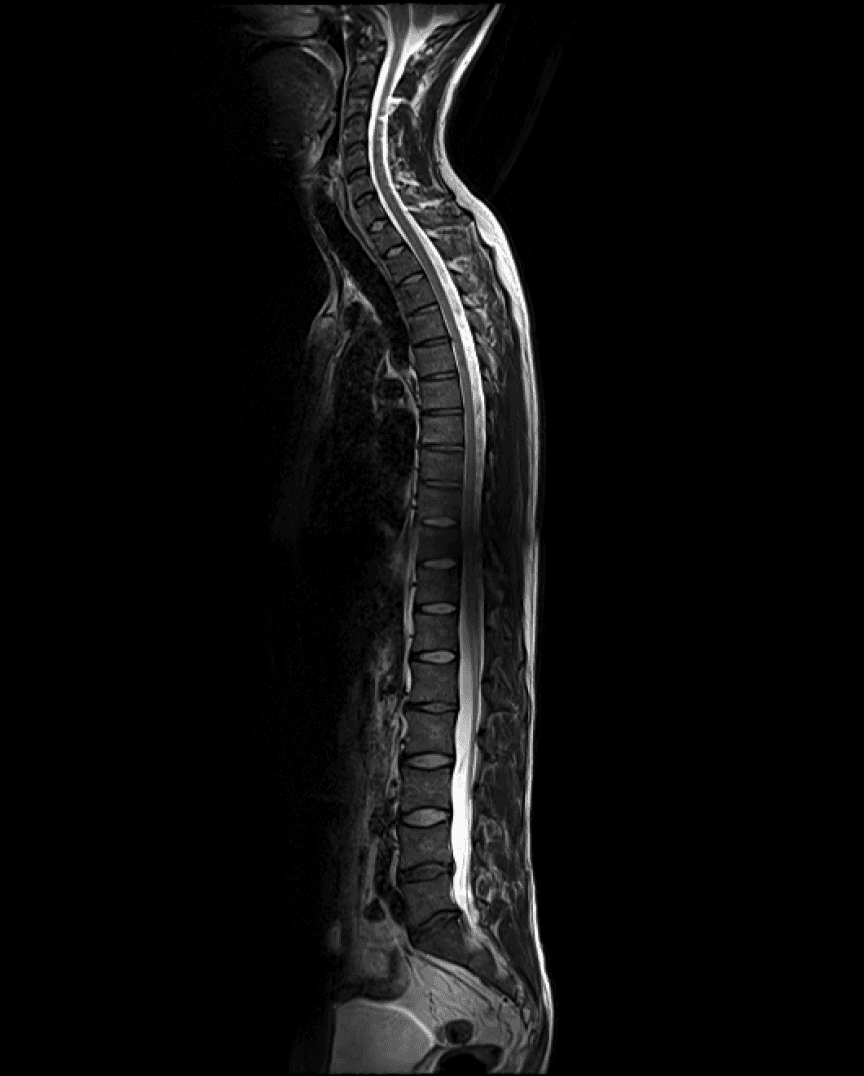

AI-based annotation of your body

Easily understand highly technical scans.

Side-by-side comparison

Track internal changes over the years.

Additional insights

Background information on biomarkers and imaging results.